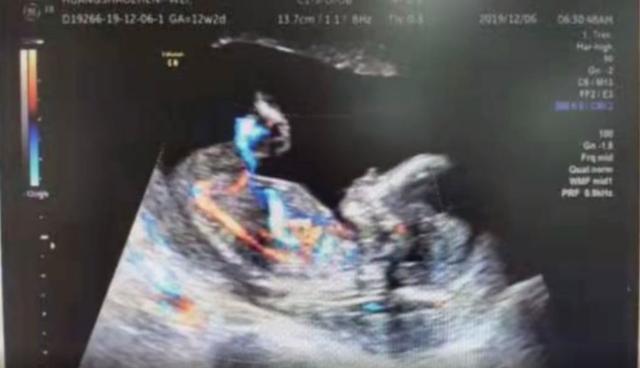

黄女士说:“当时在县城里面做的彩超,才发现不对,不是宫内孕。拿到报告单发现像是宫外妊娠,医生建议我到上一级医院检查。”

广西壮族自治区人民医院妇产科主任医师介绍,在当地刚开始检查只是早孕,找不到胚胎在哪里,大概15周多,在她的子宫腔里是没有看到胎儿,正常怀孕都是在子宫腔里的,而宫外孕95%都是长在输卵管。12月5日下午,黄女士从扶绥县人民医院转到广西壮族自治区人民医院妇科。经检查,确诊为腹腔妊娠,而且腹腔内的胎儿为活胎,已经有4个月大。